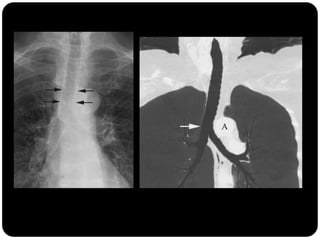

Atelectasia

 Diminuição de volume do segmento, deslocamento de uma ou mais

fissuras interlobares em direção à parte atelectasiada, desvio do mediastino

para o lado envolvido, deslocamento hilar, estreitamento dos espaços

intercostais e hiperinsuflação dos outros lobos / segmentos não atelectasiados

de forma compensatória.

Ex: Colapso do

LSD

Observar

deslocamento de

fissura!

Atelectasia do lobo

superior direito

Atelectasia do Lobo Sup. D.